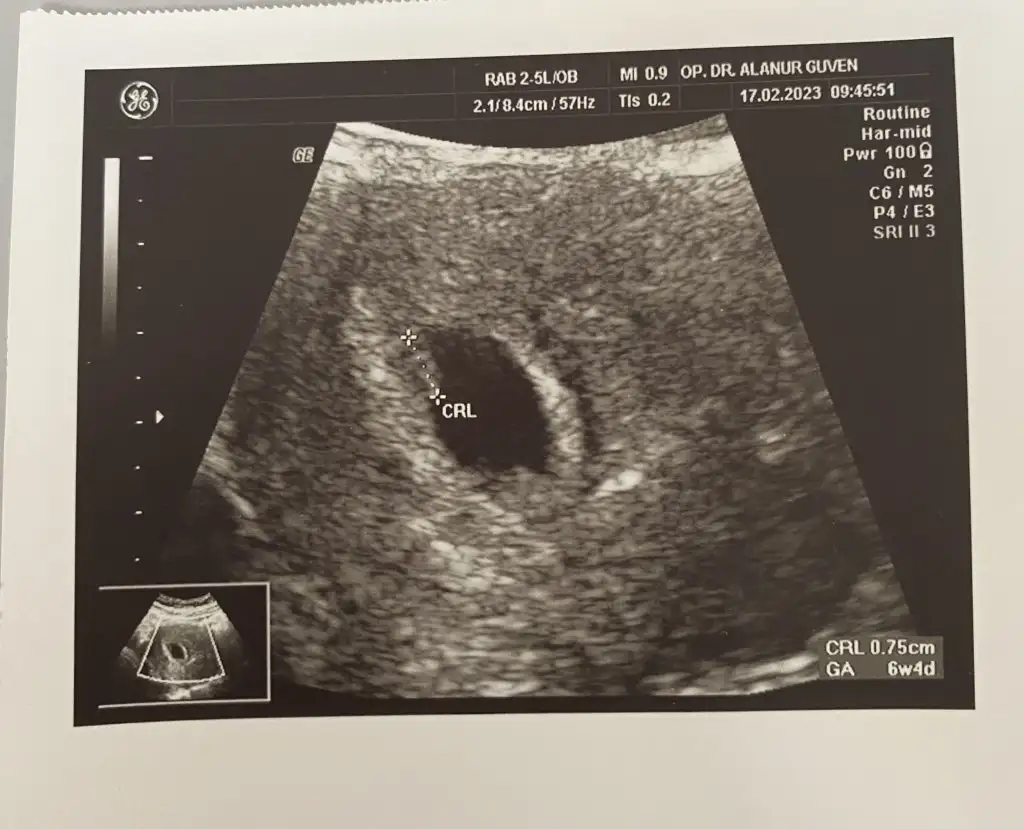

• 16793857404897884354304871002078.webp

16793857404897884354304871002078.webp

19,3 KB · Görüntüleme: 51